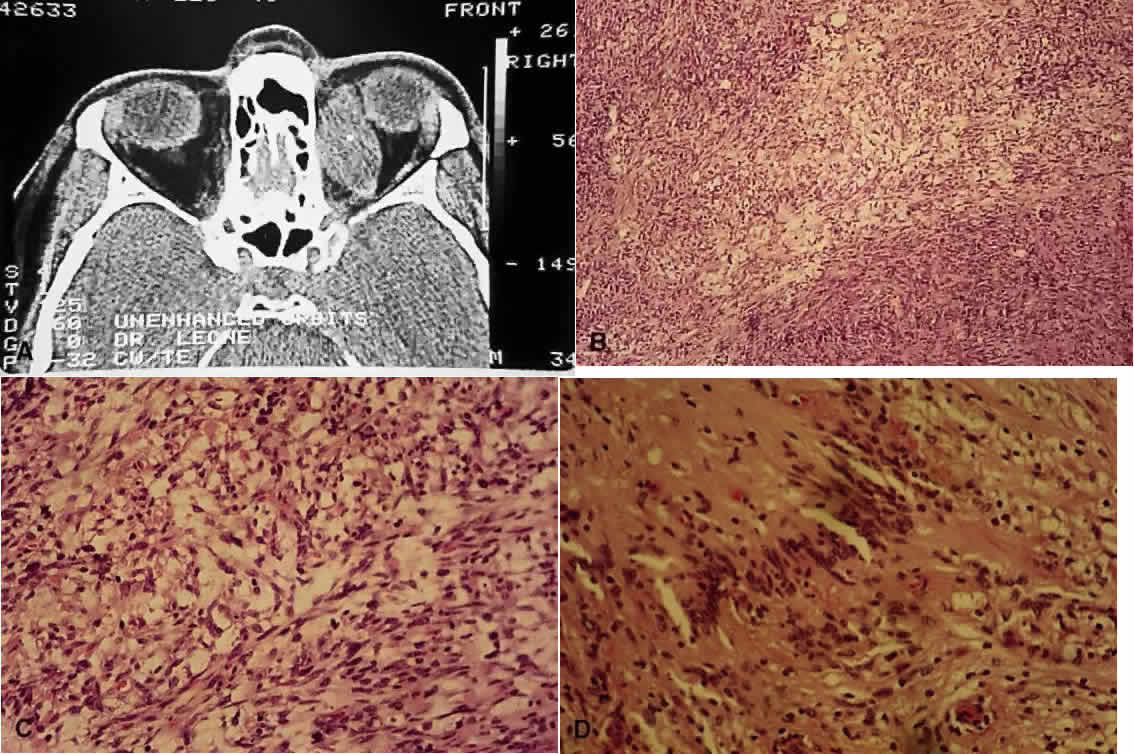

Fig. 7. Neurofibromatosis type 1. A. Clinical view of neurofibroma involving the right lids (H&E, × 7.8). B. Low-power view showing diffuse involvement of the dermis (H&E, × 31). C. Higher-power view shows infiltration and separation of striated muscle fibers (H&E, × 31). D. In another area are bundles of proliferated neural elements.

Fig. 9. Neurilemmoma (schwannoma). A. Computed tomography scan of orbital neurilemmoma. B. Low-power view showing Antoni A (more densely packed cells) and Antoni B (more mucoid, paler areas) patterns (H&E, × 10). C. Higher-power view showing Antoni B pattern (H&E, × 25). D. High-power view of a Verocay body, where the long axes of the cell nuclei line up in register (H&E, × 31).